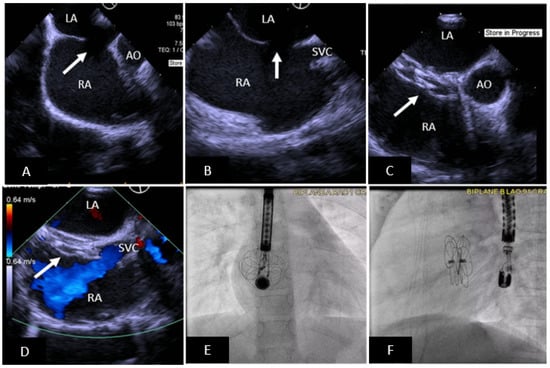

- Tandon, A.; Burkhardt, B.E.U.; Batsis, M.; Zellers, T.M.; Velasco Forte, M.N.; Valverde, I.; McMahan, R.P.; Guleserian, K.J.; Greil, G.F.; Hussain, T. Sinus Venosus Defects: Anatomic Variants and Transcatheter Closure Feasibility Using Virtual Reality Planning. JACC Cardiovasc. Imaging 2019, 12, 921–924. [Google Scholar] [CrossRef]